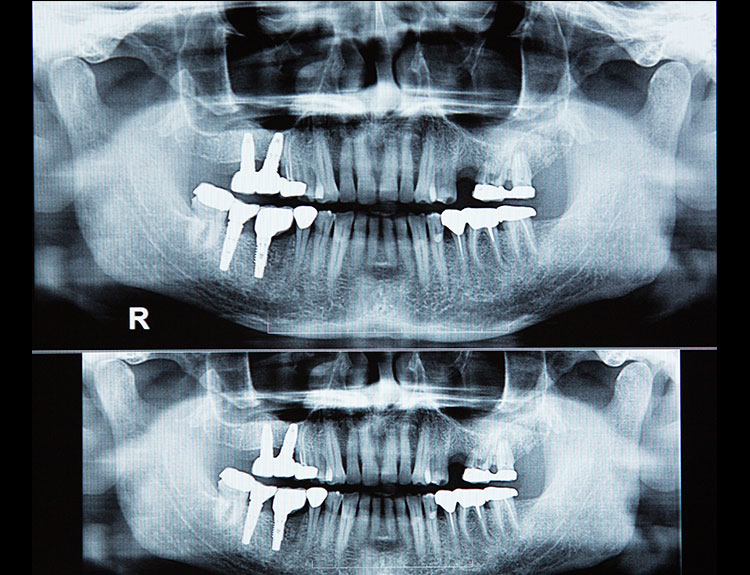

Dental implants are artificial tooth roots made of medical-grade titanium that are surgically placed into the jawbone. Once the implant integrates with the bone, a crown is fixed on top, giving you a strong, natural-looking replacement tooth.

Dental implant treatment requires specialized training and experience. Choosing a qualified Implantologist in Punjabi Bagh like Dr Sumit Dutta or Dr Harsha Dutta ensures: